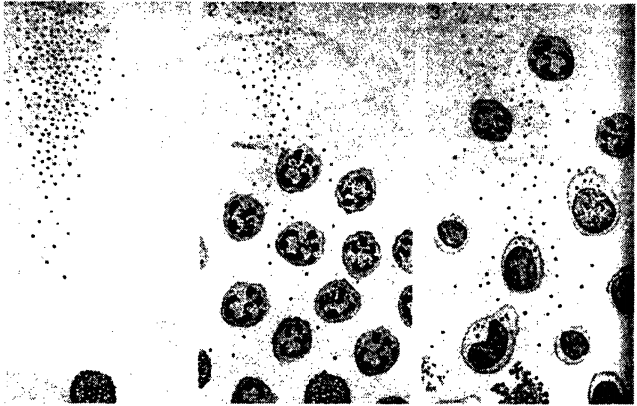

‘शत्रु' का संहारः पानीपत का पहला युद्धः 'शत्रु' को पहचानने पर अचानक प्रतिरक्षा तंत्र हरकत में आ जाता है। शत्रु को पहचानने वाले श्वेत रक्त कण (टी-सेल ) रसायनों के माध्यम से अन्य श्वेत रक्त कणों तक संदेश पहुंचा देते हैं कि शत्रु मौजूद है और हमला किया जा सकता है। शत्रु (चित्र में काले-काले बिन्दु ) की पहचान के बाद उनसे संपर्क में आने वाली विशेष किस्म की कोशिकाएं ( मास्ट सेल, पहले चित्र में नीचे की ओर ) खास तरह के रसायनों से तरह-तरह के श्वेत रक्त कणों को आक्रमण की खबर दे देती है और वे सब युद्धक्षेत्र की तरफ कूच कर देते हैं (चित्र2,3 ) और शत्रु को खेत करके निगलने लगते हैं। साथ ही वे उस इलाके में फैले लड़ाई में शहीद हुए ‘स्वयं' और 'अन्य' के टुकड़ों व रसायनों आदि का भी सफाया कर देते हैं। इस पेटूखोरी से उनमें से कई तो एकदम फूल-से जाते हैं (चित्र-4,5 )। ये श्वेत रक्त कोशिकाएं इस सब ‘माल' को एन्ज़ाइम के जरिए ऐमिनो अम्ल और शर्करा में तोड़कर पचा जाती है। परन्तु शत्रु के कुछ टुकड़े। कुछ कोशिकाओं में भविष्य के लिए बचाकर रखे जाते हैं (चित्र-6 में गोले में घिरे काले बिंदु )।

पहली बार आए शत्रु का दूसरा हमलाः दूसरी बार हमला होने पर प्रतिरक्षा तंत्र में हरकत बहुत ही तेज़ी से होती है, क्योंकि दुश्मन उनका पहचाना हुआ था। खूब सारे बड़े वाले श्वेत रक्त कण युद्धक्षेत्र में पहुंच जाते हैं। इनमें से कुछ में उसी शत्रु के पुराने रखे हुए टुकड़े भी होते हैं (चित्र-1,2 )।